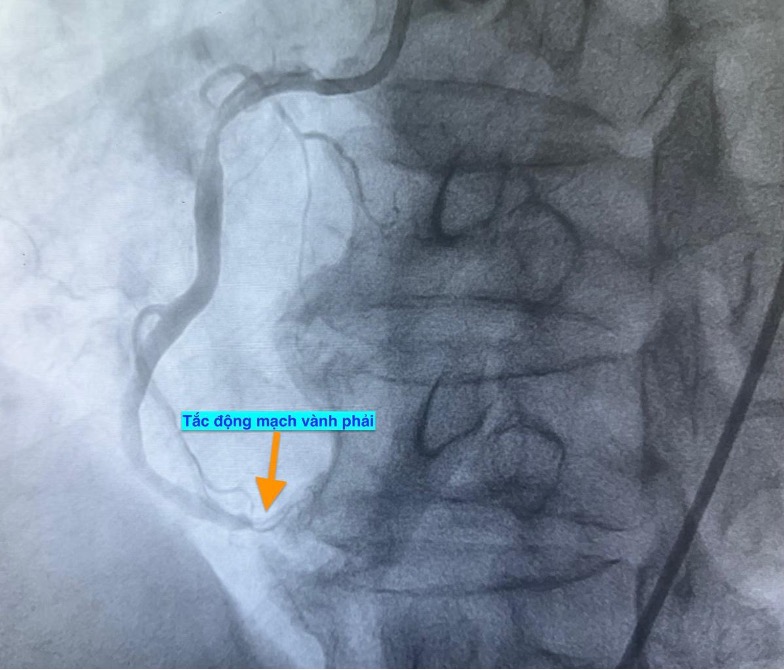

Trường hợp thứ nhất, lúc 0 giờ 34 phút ngày 14.11, nam bệnh nhân 51 tuổi vào bệnh viện vì mệt và khó thở. Chụp mạch vành phát hiện bệnh nhân bị tắc hoàn toàn động mạch vành phải.

Trường hợp thứ hai, lúc 9 giờ 5 phút, nam bệnh nhân 53 tuổi nhập viện vì chóng mặt và nóng rát thượng vị. Điện tâm đồ ghi nhận nhồi máu cơ tim cấp vùng dưới. Kết quả chụp mạch vành xác định bệnh nhân cũng bị tắc động mạch vành phải.

Trường hợp thứ ba, lúc 15 giờ 53 phút, nam bệnh nhân 78 tuổi nhập viện vì đau ngực. Bệnh nhân cho biết đau ngực từng cơn trong 3 ngày, ngày nhập viện thì đau ngực liên tục. Điện tim gợi ý nhồi máu cơ tim cấp; chụp mạch vành cấp cứu phát hiện bệnh nhân cũng tắc động mạch vành phải.

Hình ảnh chụp mạch vành cho thấy các bệnh nhân bị tắc mạch máu tim (do mảng xơ vữa, huyết khối) dẫn đến tình trạng thiếu máu cục bộ và nhồi máu cơ tim cấp